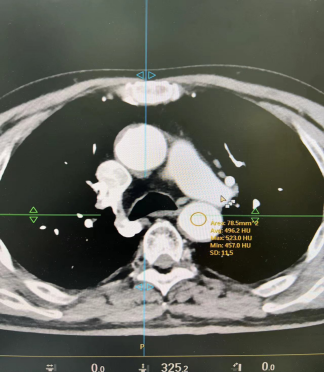

血管CTA:相同体重的患者 造影剂用320mg/ml和370mg/ml 都用4.0ml/s流速注射60ml对比剂

从上述图像可以看出,370造影剂明显比320造影剂CT值要高,显示要好

370mg/ml 60ml造影剂流速4.0ml/s和320mg/ml 60ml造影剂流速提高到4.6ml/s时CT值对比

我们可以看出,320mg/ml的造影剂流速提高的4.6ml/s时CT值和370mg/ml流速4.0ml/s时CT值接近,这就意味着单位时间内碘含量增加有利于血管强化,浓度较低的造影剂,通过增加流速血管强密度增高